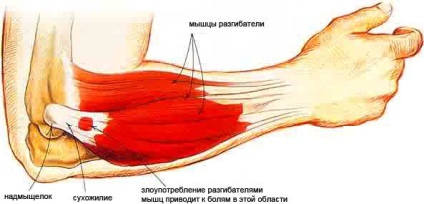

Extensor izmok váll

Ebbe a csoportba tartoznak a hátizmokat. Ezek közé tartoznak:

- Triceps.

- Elbow izom.

Emberi Tricepsz dvusustavnyh osztályába tartozik, és egy 3 fej hátulján a vállát. Ez a szövet több funkciót végez:

- Működteti váll berendezésben.

- Serkenti a kiterjesztését a váll egységet.

- Úgy működik, könyök.

On ízület alatti penge nyúlvány kapcsolódik hosszú feje és mediális és laterális - hátoldalán a lapockák. Ezek található mindkét oldalán a radiális ideg és körülveszik az intermusculáris septum. Ezután irány a forraljuk 1 ín, amelynek végződése az alkar és a könyök van csatlakoztatva a élrátét. Tricepsz megkönnyíti kiterjesztése a könyök elem. Amikor a kárt a beteg nem tud meghajlítani vagy kiegyenesedik a könyökét. Ebben az esetben az a személy, tapasztalatok erős fájdalom a könyök. Ha a beteg a veleszületett deformitás (izom rövidebb vagy hosszabb), a kéz nem lesz, amíg a végén könyök, vagy kiegyenesedik fog természetellenesen hajlítsa kifelé. Ebben az esetben a beteg nem mindig érzi a fájdalmat. Az ilyen deformáció műtéttel.

alkar extensor

Könyök tartalmaz egy eszközt extensor Carpi. Ezek az izomrostok vannak a műszerfal, az alkar és leereszkedik. csukló extensor csatlakozik a csont és a mediális felhalmozódását, és ezután ráhelyezzük a metacarpalis csont. Ezek az izomrostok világosan látható a betegek jó izomzattal. Ezek teljesen szomszédos a csonttal. Ehhez képest a készülék a könyök, csukló extensor gyengék nyomaték. A fő feladat az izomszövet - kiterjesztés ecsettel.

Hosszú orsócsonti csuklófeszítő izom kapcsolódik a váll csontszövet és lemegy a másik alá izmokat. Jó látni az izomrostok is elég ritka. Vége az izom csatlakozik a 2. metacarpalis. Extensor funkció gerenda -, hogy ellenőrizzék az intézkedés az ecset. Munkahelyen a könyök extensor apparátus nem érinti jelentősen. De távolléte nagyban megnehezíti a munkát az egész karját. Ha az extensor sérült, az a személy fájdalmat érez az első helyi természetére, de akkor terjed az egész kezét.

Az izmok felelősek kiterjesztése a könyök

Rövid orsócsonti csuklófeszítő izom több, mint egy hosszú berendezés. Ez izomszövet van szerelve a felkarcsont csont és továbbra is 3 metacarpalis csont. Anatomy ezen készülék mozgását igen egyszerű. Eltekintve attól a ténytől, hogy az izomszövet kiterjeszti a csuklóját, azt is állítja fokát eltávolítását az oldalon. Abban az esetben, kár, hogy a feszítő beteg képtelen forgatni a kezét, és elvégzi az egyszerű manipuláció kezét.